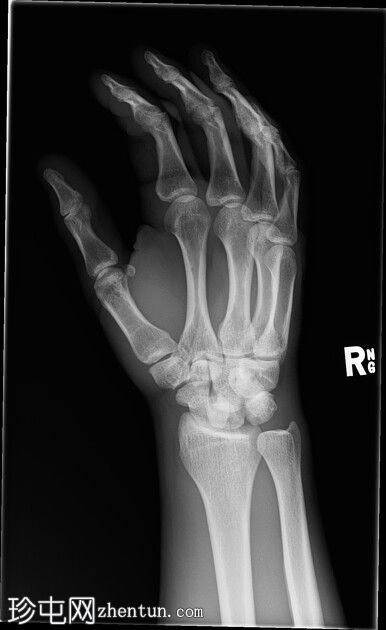

右腕

X光片

正面

斜位

侧面

前后位:舟月骨间隙增宽,月骨呈三角形。侧面显示头状骨与月骨背侧脱位,月骨与桡骨远端保持正常排列。符合月骨周围脱位的特征。无合并腕骨、桡骨或尺骨骨折。腕部软组织肿胀。